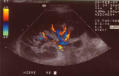

Links oben Halsschlagader, oben Beinarterien, links Nierengefäße

Unsere Praxis ist u.a. mit 4 hochwertigen Farbdopplersonographiegeräten ausgestattet,

Hiermit können Erkrankungen der Hals-, Hirn- sowie der Arm, - Nieren- und Beingefäße einfach, risikolos und mit hoher Zuverlässigkeit untersucht werden.